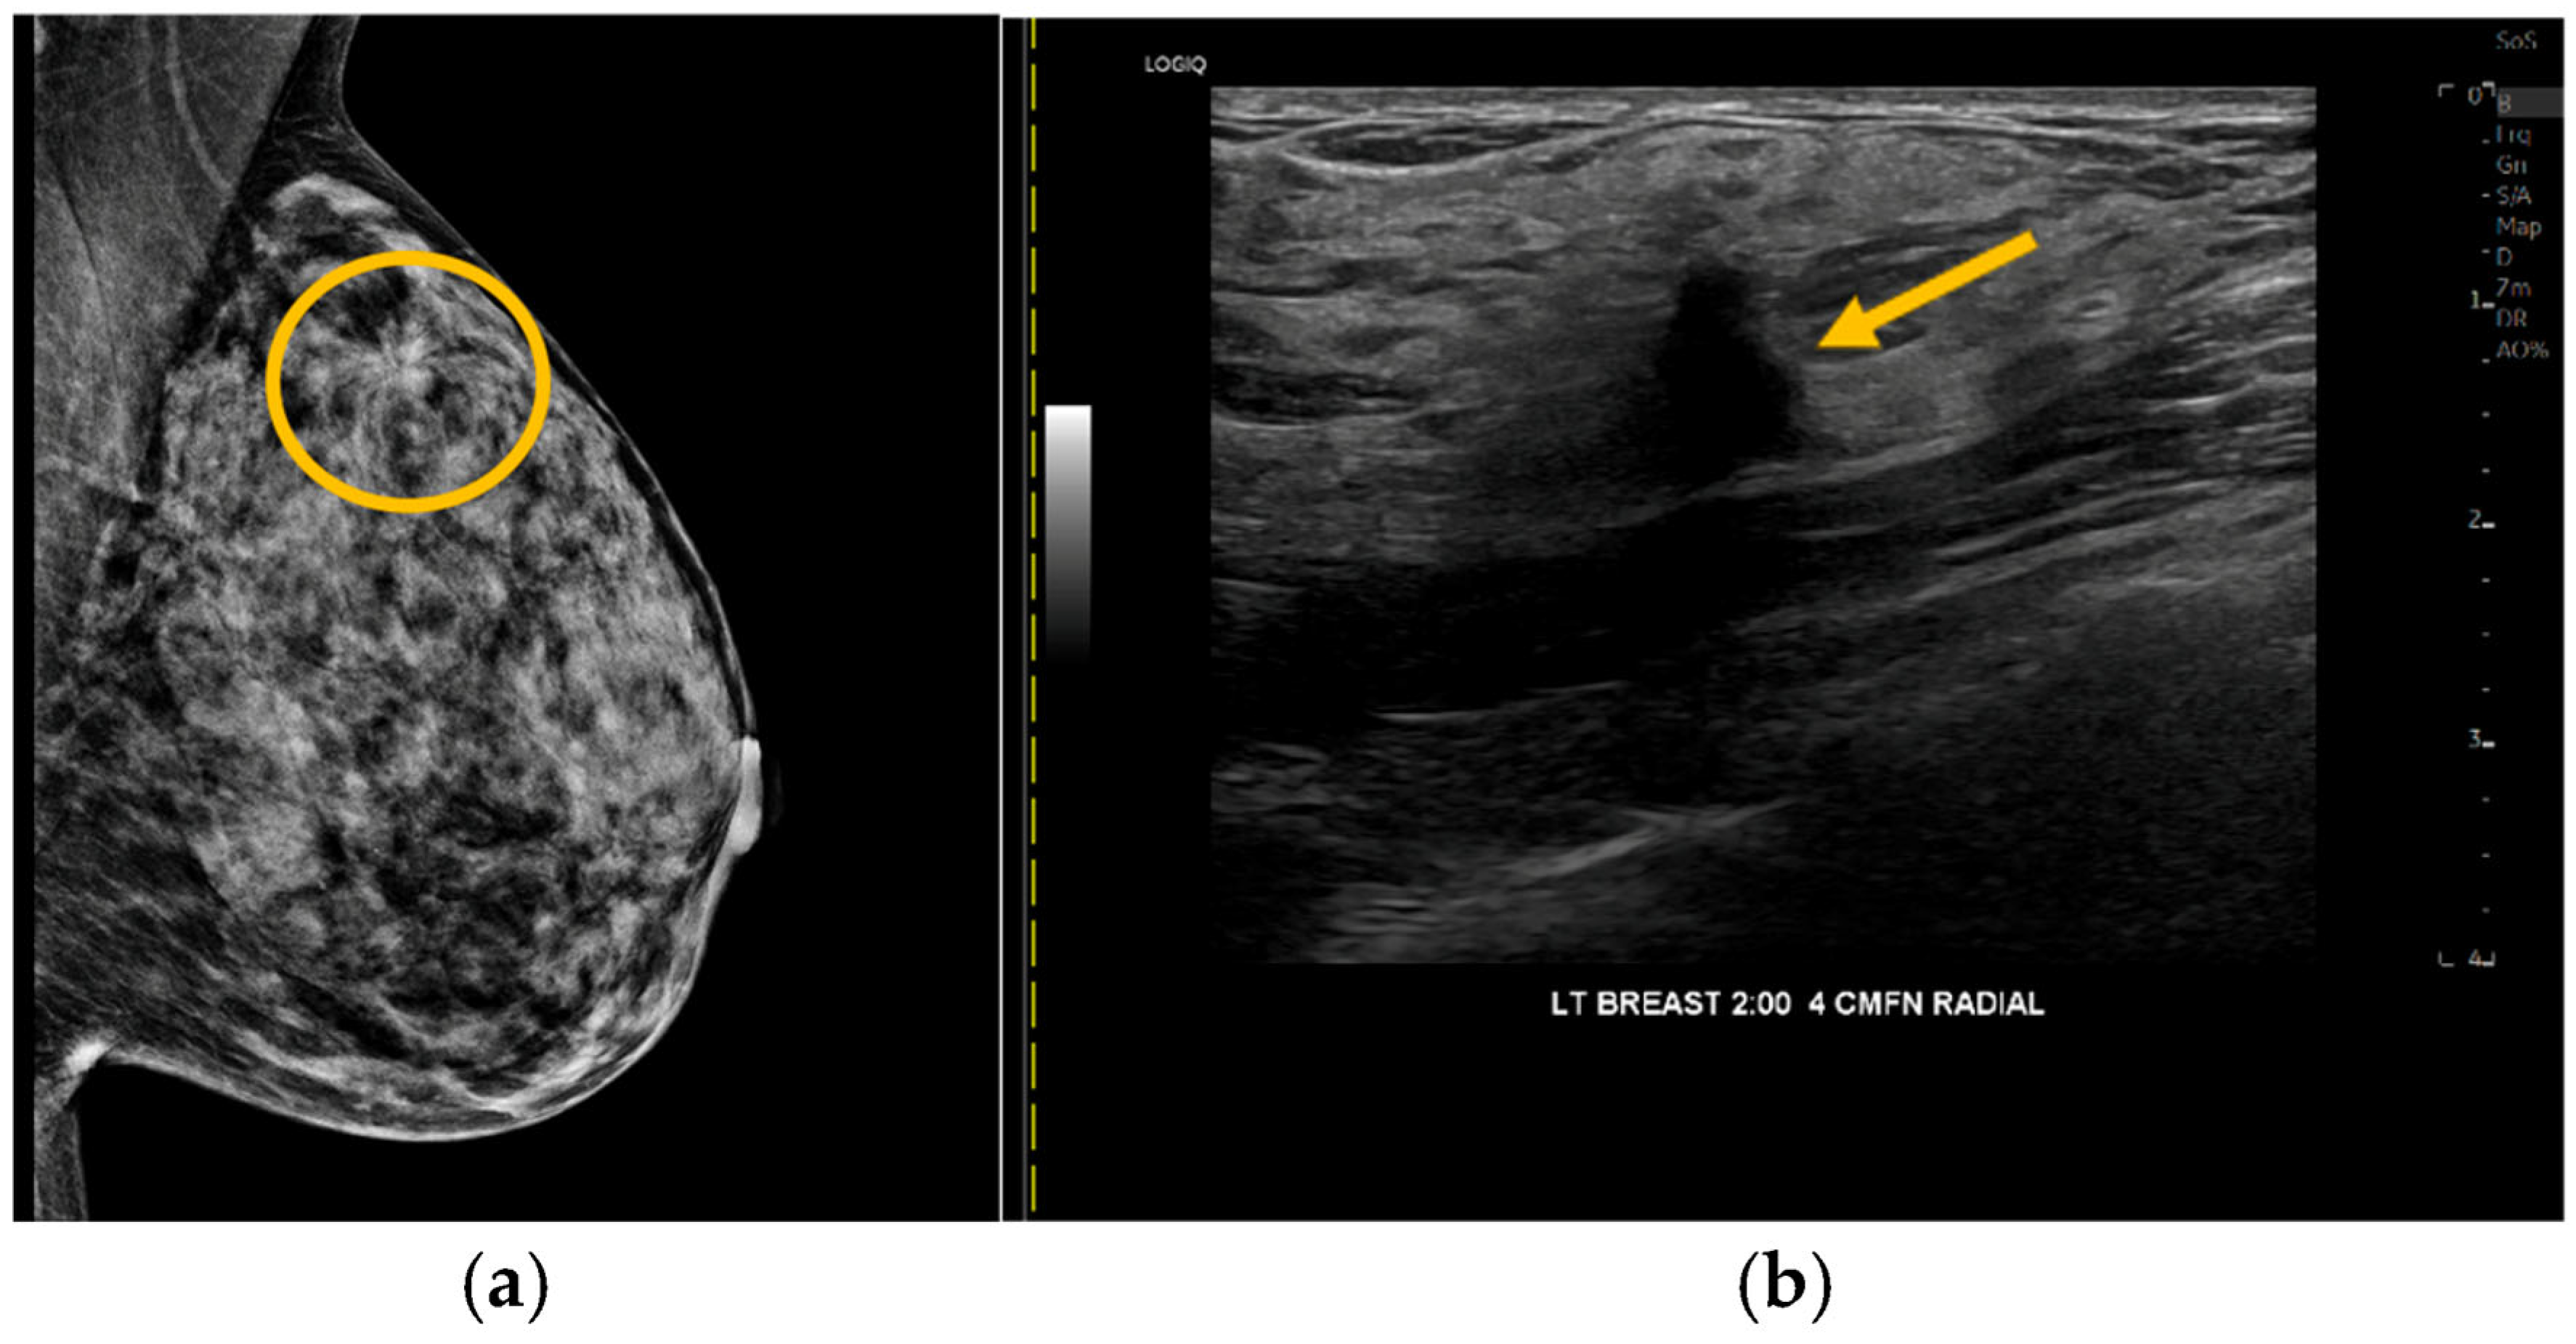

| Malignant | mass | positive | positive | IDC 1 |